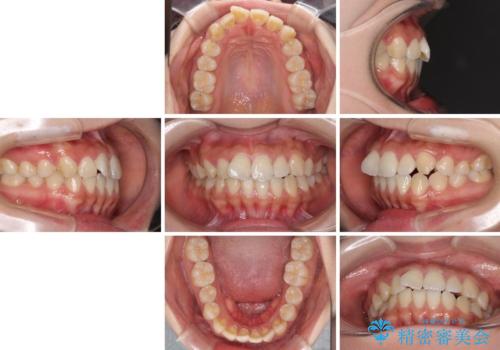

軽微な歯列不正をワイヤー矯正で整える

- 上顎歯列と下顎前歯の叢生を気にして来院された患者様です。

上顎からワイヤー矯正を開始し、終了間際から下顎前歯の叢生解消するよう計画しました。

部分矯正でしたが、咬み合わせに違和感が出ることなく気になる部分を改善させることができました。